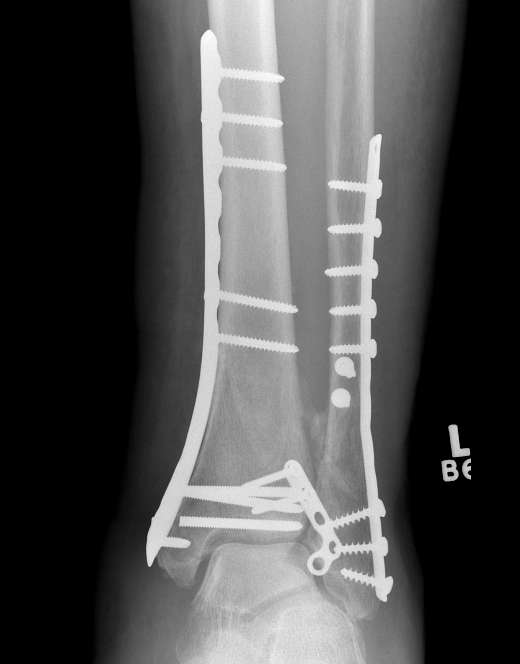

ORIF with Plates

Principle

Restore articular surface

Fix articular surface to metaphysis

Anatomical Plates

Medial plateAnterolateral plate

Synthes medial plate                               Synthes anterolateral plate

Tibial Plafond CT AxialTibial Plafond CT SagittalPlafondTibial Plafond ORIF APTibial Plafond ORIF Lateral